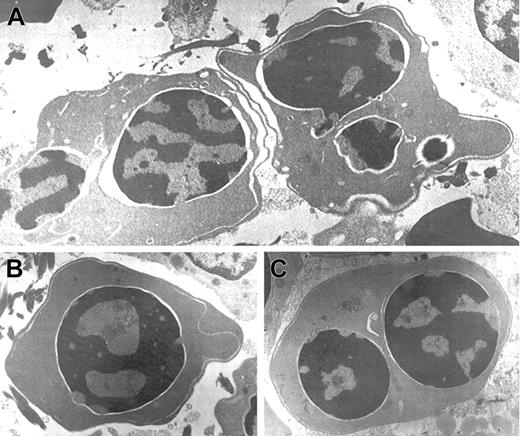

Electron micrographs of several bone marrow late erythroblasts.

Multinucleate erythroblasts showing striking “double membranes” with partial dilatation of the intramembranous space (A). Erythroblasts revealing nondilated cisternae (B,C). Late erythroblast depicting spongy heterochromatin with numerous “punched out” areas (B). Binucleate erythroblasts showing large areas of nuclear membrane without attached heterochromatin (C). Uranyl acetate and lead citrate stain. Original magnification: A, × 10 600; B and C, × 18 000).

Electron microscopic aberrations were more prominent in late erythroblasts (Figure 2). The nuclear outline was often undulated or lobulated, and the nuclear membrane–associated heterochromatin was frequently absent over large areas of the nuclear membrane. In some cells, the heterochromatin was spongy and showed numerous “punched out” areas. The main cytoplasmic anomaly was the presence of abundant cytoplasmic membranes that are composed of excessive smooth endoplasmic reticulum. These characteristic cisternae usually ran parallel beneath the cell outer membrane producing the so-called “double membrane.” The dilatation of the space between the 2 layers of these cytoplasmic membranes was frequently observed, as was the dilatation of the space of the nuclear membrane.